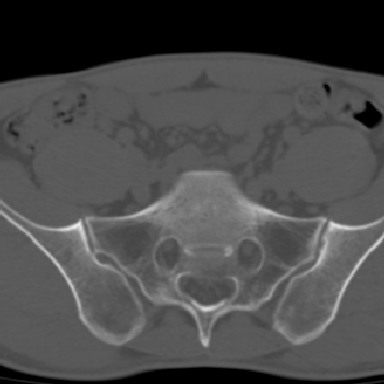

m 30 腰背部不适半年; 清晨时僵硬; 活动症状有所改善

双侧骶髂关节下2/3关节面模糊,毛糙,可见小囊状骨质破坏区.支持强直性脊柱炎.

强直性脊柱炎的早期改变!不仅表现为双侧骶髂关节,第5腰椎与骶椎间的关节突关节也有类似改变。

双侧骶髂关节下2/3关节面模糊,毛糙,髂骨侧可见小囊状骨质破坏区,骶髂关节间隙增宽(软骨破坏期)。支持早期强直性脊柱炎。

双侧骶髂关节下2/3关节面模糊、毛糙,可见小囊状骨质破坏区,呈虫咬状改变,周围可见增生硬化.支持强直性脊柱炎早期表现.

双侧骶髂关节髂骨面硬化,毛糙,小囊变,属于早期强直性脊柱炎